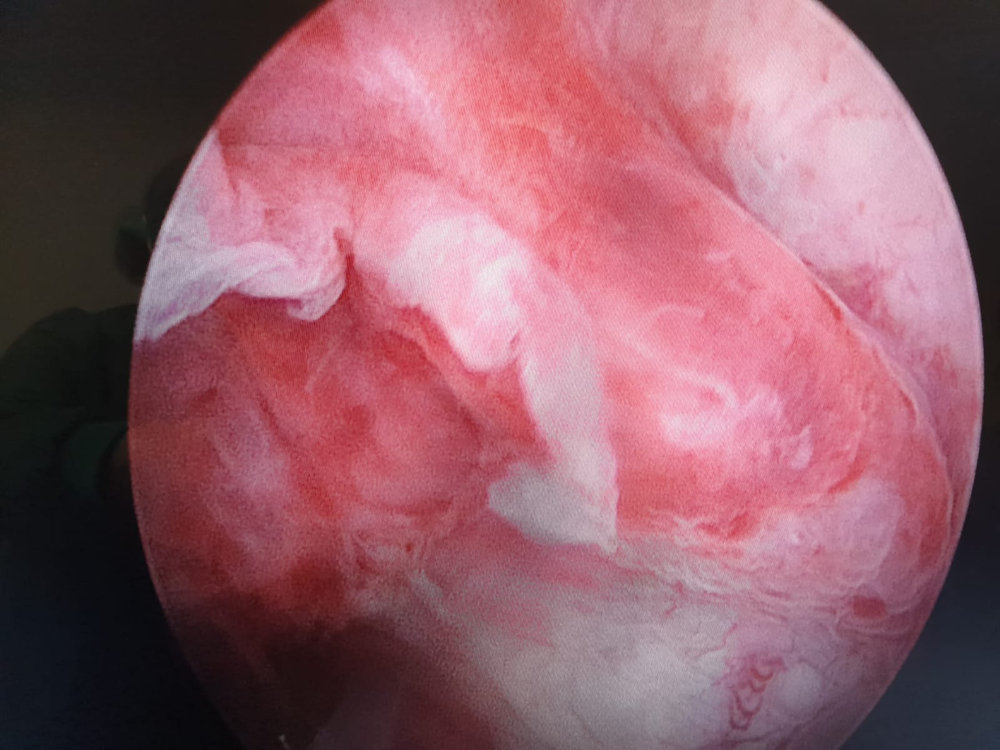

Histeroskopi rahim içini ve tüplerin rahime açılan kısmının optik kamera eşliğinde incelenmesidir. Hem tanı hem de cerrahi amaçlı kullanılır. İnfertilite(kısırlık), tekrarlayan düşüklerin nedenlerinin araştırılmasında, anormal adet kanamalarının nedeninin araştırılmasında ve rahim içi patolojilerin tespit ve tedavisinde histeroskopi önemli bir tanı aracıdır.

Genel veya lokal anestezi altında rahim ağzı genişletilerek içeriye kamera yerleştirilir.Rahim içinin daha iyi gözlenebilmesi için sıvı verilerek rahim içi doldurulur. Böylece yer kaplayan herhangi bir kitle, polip, yapışıklık, band olup olmadığı araştırılır. Histeroskopun ucundaki kesici veya yakıcı uygun aletler ile gerekirse ameliyat da yapılabilir